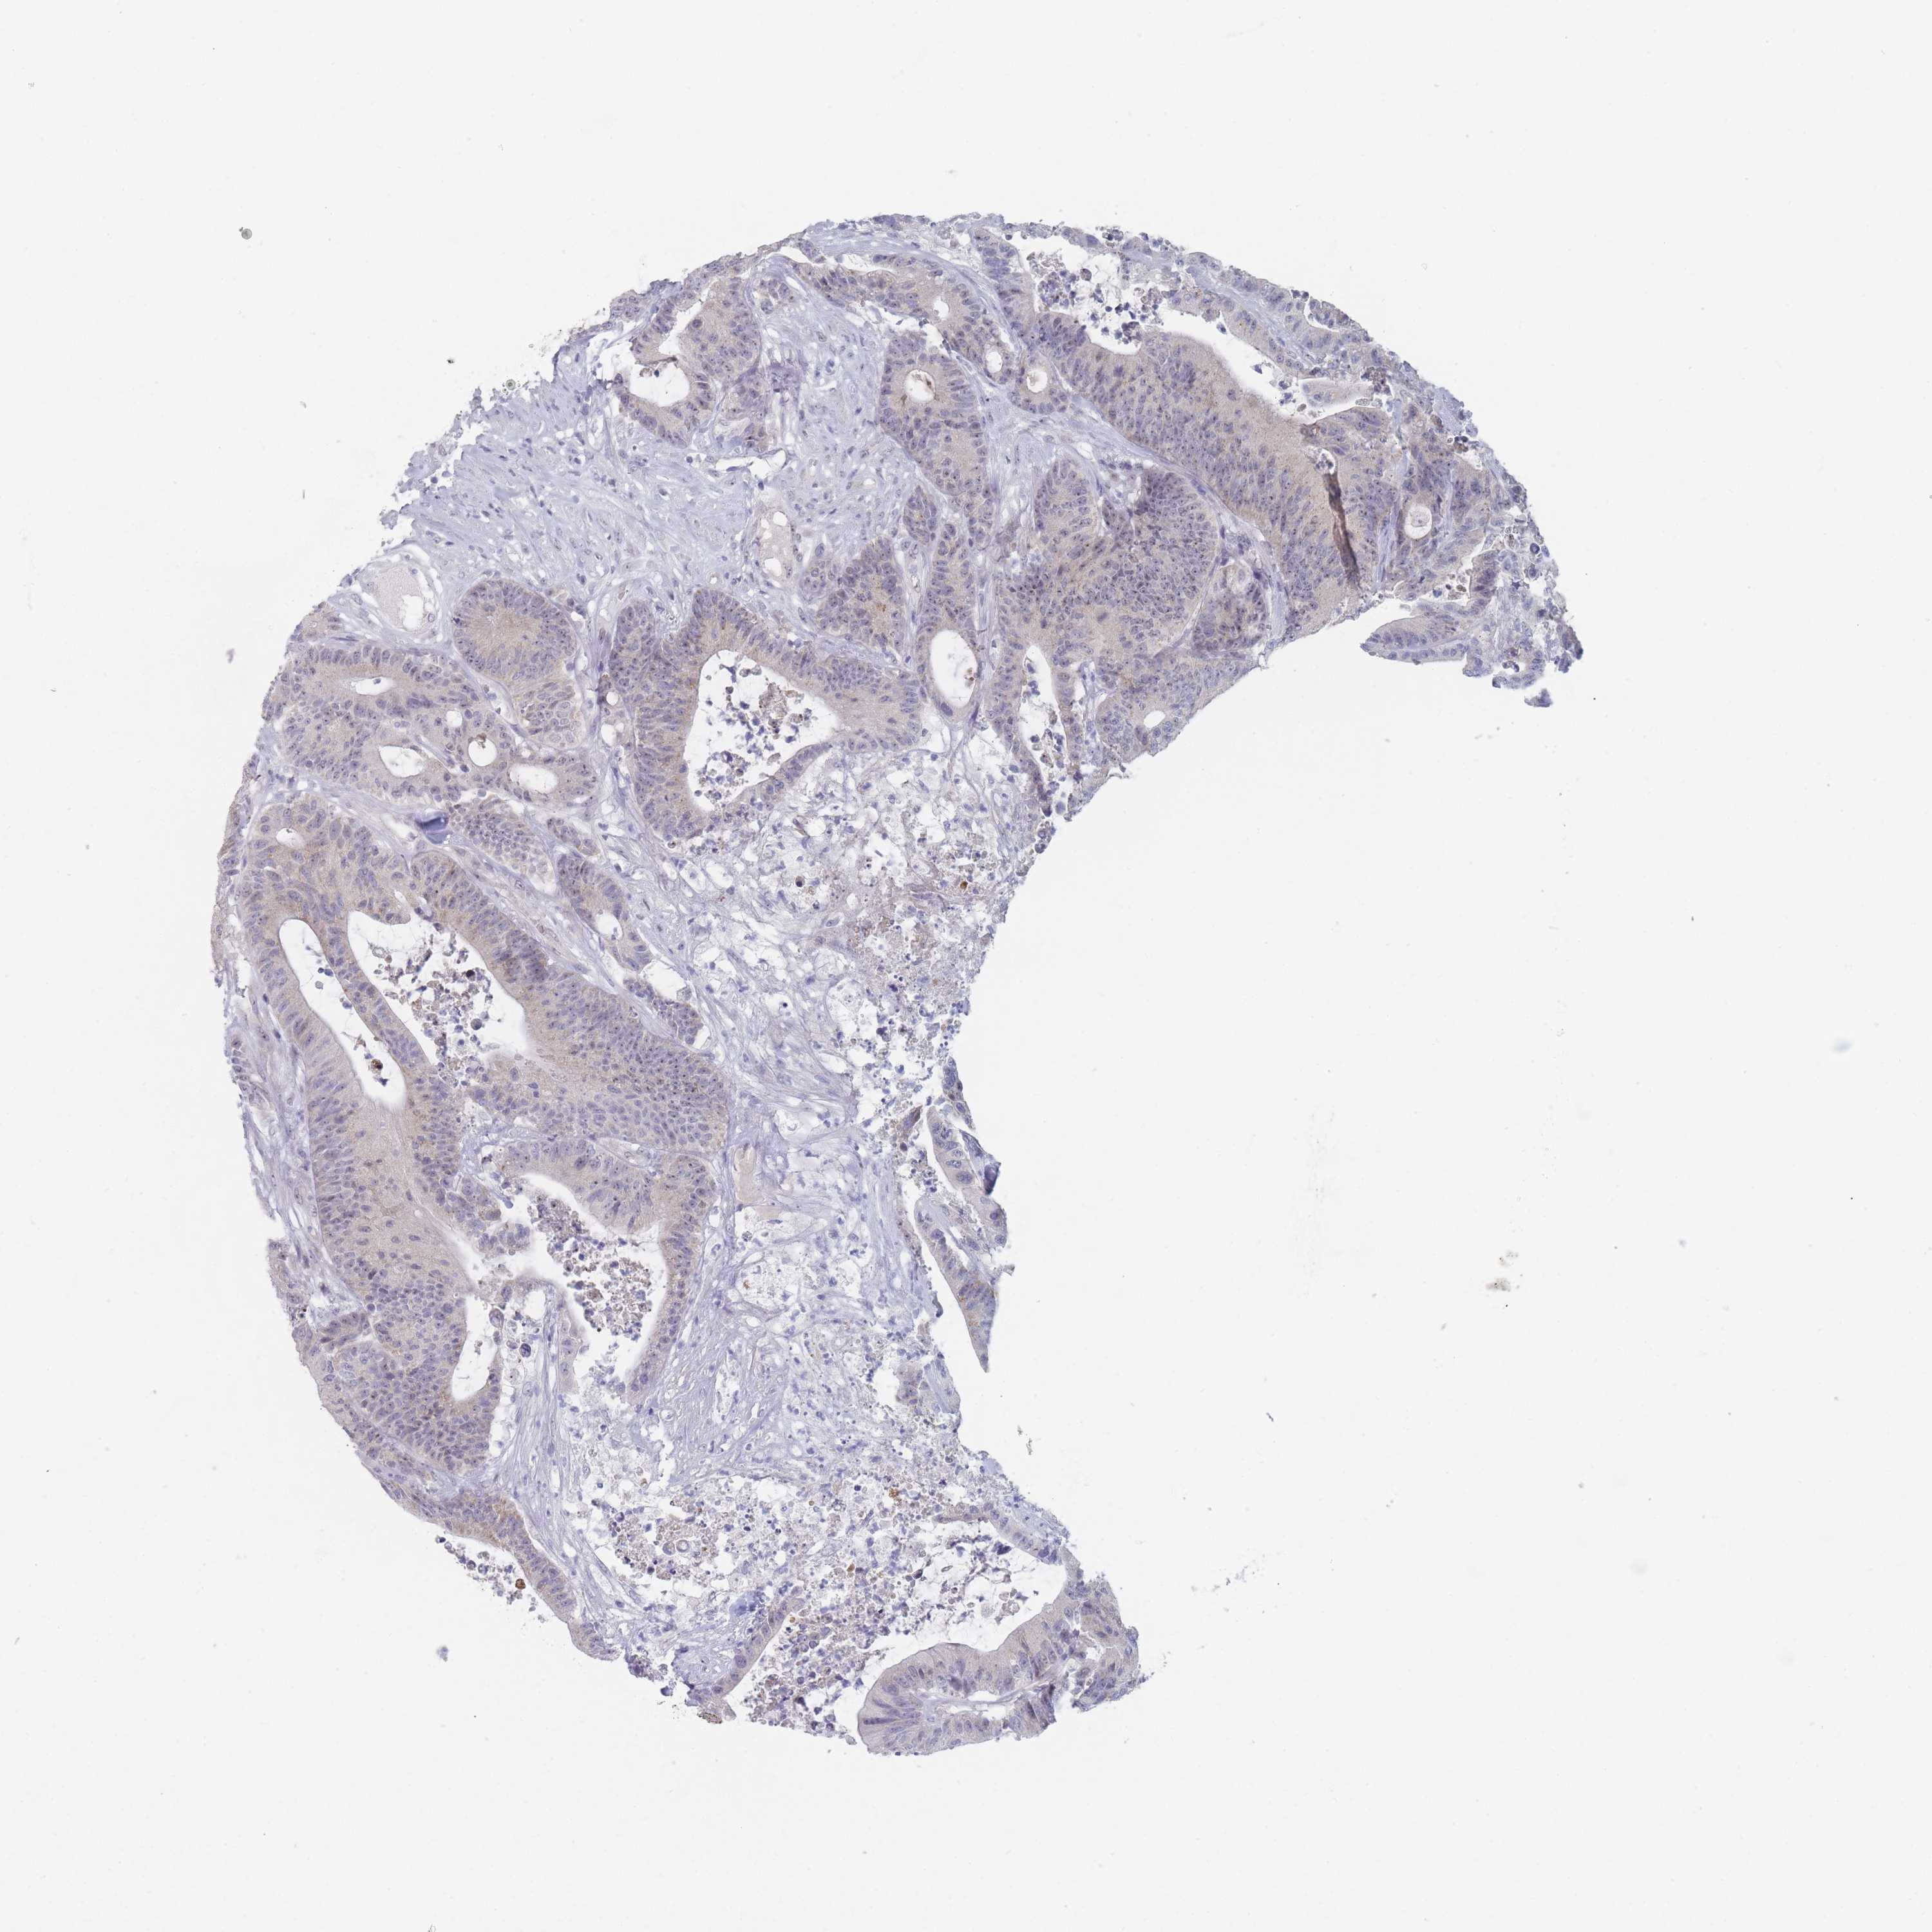

Colorectal cancer

Rectum adenocarcinoma